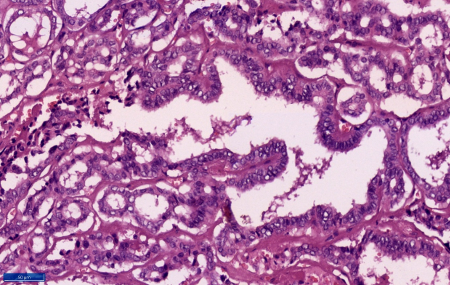

consistency. At microscopy sections showed a duct

made up of fibrous wall with extensive calcific

areas. The lumen of the duct showed a tumor

comprising of cells in predominantly papillary

pattern along with occasional follicle formations.

Individual cells lining the papillae and the

follicles showed crowding and overlapping. These

tumour cells demonstrated moderate eosinophilic

cytoplasm, mild nucleomegaly, round to oval with a

single nucleus showing nuclear clearing,

margination of the chromatin and occasional intra

nuclear grooves. Scanty mitosis were also noted.

The wall of the duct shows normal thyroid

follicles and chronic inflammation. The tumour

cells were embedded in the duct walls at places.

However, tumour cells were not extending beyond

the duct. (Figure 3-6) Hence a final diagnosis of

papillary carcinoma of thyroid-classic type (PTC),

arising in a thyroglossal duct cyst was made.

| Figure

5: Section shows tumour cells trapped

within the cyst wall. (Haematoxylin and

Eosin, x 100) |

Figure

6: Section shows tumoral papillae line by

tumour cell showing nuclear crowding,

overlapping, nuclear clearing and

grooving. (Haematoxylin and Eosin, x 400) |